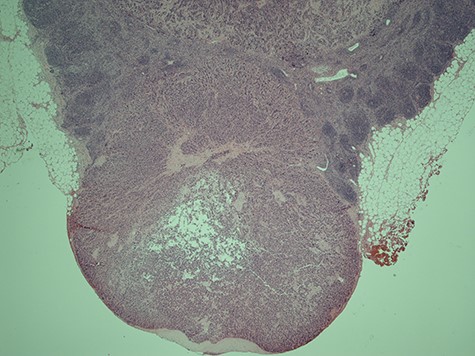

Initial examination showed soft, non-tender abdomen. Rectal examination revealed a suspicious anterior rectal mass. An urgent colonoscopy was therefore arranged and biopsies returned to show evidence of ulcerative colitis (UC) but no masses/neoplasia. Despite establishing the diagnosis and initiating appropriate Asacol and mesalazine treatment, she subsequently became significantly unwell and presented through the emergency department with severe abdominal pain, distention and vomiting. Physical examination revealed a blood pressure of 101/67 mmHg, HR of 123 beats/min, respiration rate of 24 breaths/min and saturations of 90% in room air. Computed tomography (CT) abdomen and pelvis not only showed descending colon inflammation and severe terminal ileitis but also moderate volumes of free fluid with extensive intra-abdominal inflammation. Initial laboratory blood tests were Hb 132, WBC 8.23, Plts 44, lactate 1.2, CRP 72, K+ 3.3, AST 46, Albumin 37. PR bleeding continued and haemoglobin levels began to drop out of proportion, reaching a low of 70 g/l as well as derangement of her coagulation studies. She was then escalated to critical care given her persistent hypotension and DIC, but ultimately she underwent emergency laparotomy. In theatre, we identified a massive retroperitoneal haematoma and approximately 30 cm of gangrenous terminal ileum. Patchy gangrene tissue of the ascending and descending colon was noted with preservation of the sigmoid colon. A subtotal colectomy was performed with end ileostomy and the cross-stapled sigmoid stump was left in situ. Additionally, two large (3 cm) abnormal mesenteric lymph nodes were also identified adjacent to the DJ flexure. These were resected for histological analysis. Histology of the lymph node surprisingly showed evidence of metastatic neuro-endocrine carcinoma with characteristics of solid trabecular growth and moderate nuclear pleomorphism (Figs 3 and 4). Post-operatively, she underwent a number of investigations in hope to identify the primary, as well as tests to identify the cause of the thrombosis.

Histological slice of the specimen acquired on the second lymph node removal.

A histological slice of the resected second lymph node tumour; viewed under x20 power.